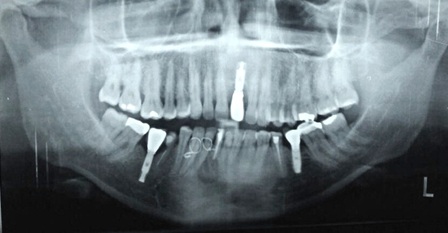

O objetivo deste estudo foi descrever uma técnica de tratamento conservadora, cuja conduta preconizada foi a realização da descompressão seguida pela enucleação cística através do relato de um caso de cisto periapical de grande extensão. Paciente de 50 anos de idade, melanoderma, apresentando cisto periapical com aproximadamente 4,5 cm em seu maior diâmetro associado ao incisivo central inferior esquerdo. Na primeira etapa do tratamento foi realizada descompressão cística e biopsia incisional, cujo exame histopatológico confirmou o diagnóstico clínico. Após 25 semanas de acompanhamento, houve uma considerável regressão do tamanho da lesão e a mesma foi enucleada sem comprometimento dos elementos dentários envolvidos e dos tecidos adjacentes. O relato de caso evidenciou que o tratamento cirúrgico e conservador pode ser um recurso em cistos periapicais de maior dimensão, sendo importante a cooperação do paciente no acompanhamento pós-operatório.